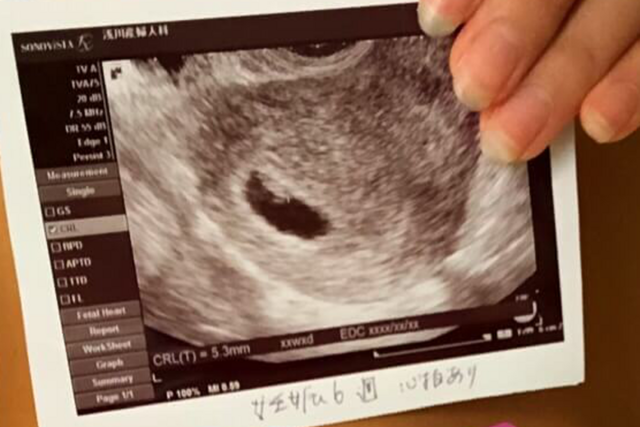

6週3日(6w3d・性別不明)|nori1515 さん(31歳)

エコー写真撮影時のエピソード:

前の週から急に吐き気とムカムカするつわりのような症状が続き、検査薬で陽性も出ていたので妊娠かなと思ってはいましたが、実際産婦人科受診するまではうれしさと同時に無事妊娠してるのかな、子宮内妊娠だろうかと不安な感情が大きかったように思います。産婦人科でエコー写真を見たとき、7mmという小ささの赤ちゃんが見えてやっと私たちのもとに来てくれたんだととてもうれしかったのを覚えています。主人もとても喜んでくれて、喜ぶ顔を見たらつらいつわりも頑張って乗り越えようと強く思いました。まだ安心は出来ないけど、このまますくすく大きくなるのを祈りつつ、安静に過ごしていきたいと思います☺️